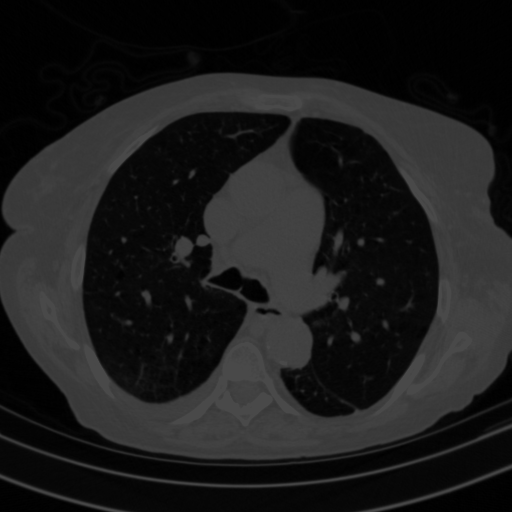

4Γ—3 grid: Rows show different image types (Original NATIVE, Reconstructed NATIVE, Original VENOUS, Generated VENOUS), Columns show windowing techniques (No Window, Lung Window, Mediastinum Window)

Generated VENOUS CT scan (A→B translation)

Lung window (WL -600, WW 1500 β†’ Low βˆ’1350, High +150)

Mediastinum window (WL 40, WW 400 β†’ Low βˆ’160, High +240)